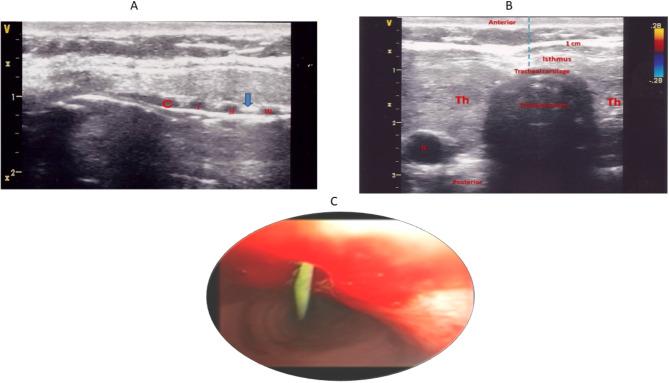

Percutaneous dilatational tracheostomy (PDT) is a common procedure for mechanically ventilated patients in the intensive care unit (ICU). This study compared the real-time ultrasound-guided PDT using a laryngeal mask airway (LMA) with the standard bronchoscopy-guided PDT technique in ICU patients requiring elective tracheostomy.

This randomized controlled study was conducted at Ain Shams University Hospital's Critical Care Department from December 4th, 2021, to December 3rd, 2022. The study population included 60 critically ill patients admitted to the ICU. Thirty patients were randomly assigned to the real-time ultrasound-guided LMA-assisted group, and 30 patients were randomly assigned to the bronchoscopy-guided technique. The primary study outcome was the procedure time, and the secondary outcomes included procedure-related complications rate and cost-effectiveness.

The real-time ultrasound-guided LMA-assisted group had significantly shorter procedure time (median 17 [IQR: 15-20] min vs. 35 [IQR: 28-39] min, p < 0.001) and lower equipment damage (0% vs. 20%, p = 0.024) during the procedure compared to the bronchoscopy-guided group. Additionally, the cost of tracheostomy was significantly lower in the real-time ultrasound-guided LMA-assisted group (median: 300 vs. 800 USD, p < 0.001). The real-time ultrasound-guided LMA group had a lower major complications rate than the bronchoscopy-guided group (36.7%) vs. 3.3%, p = 0.002).

The study demonstrated that real-time ultrasound-guided LMA-assisted PDT had shorter procedure time, reduced equipment damage, lower costs, and was associated with lower complications when compared to the bronchoscopy-guided technique. These findings suggest that ultrasound guidance can enhance the efficiency and cost-effectiveness of PDT procedures.